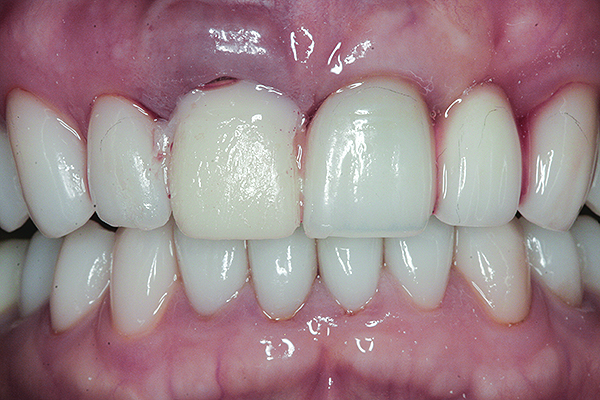

A 63-year-old female patient presented with mobility of her right maxillary incisor, tooth No. 8, secondary to endodontic therapy (Figure 1). Her medical and dental histories were non-contributory. Clinical and radiographic evaluations revealed an 8-mm probing depth on the palatal aspect. The tooth was deemed to be fractured (Figure 2). The treatment plan accepted by the patient was for extraction, immediate implant placement, and immediate provisional restoration, if possible.

Fig 1. Preoperative clinical photograph of fractured maxillary right central incisor (tooth No. 8).

Figure 1